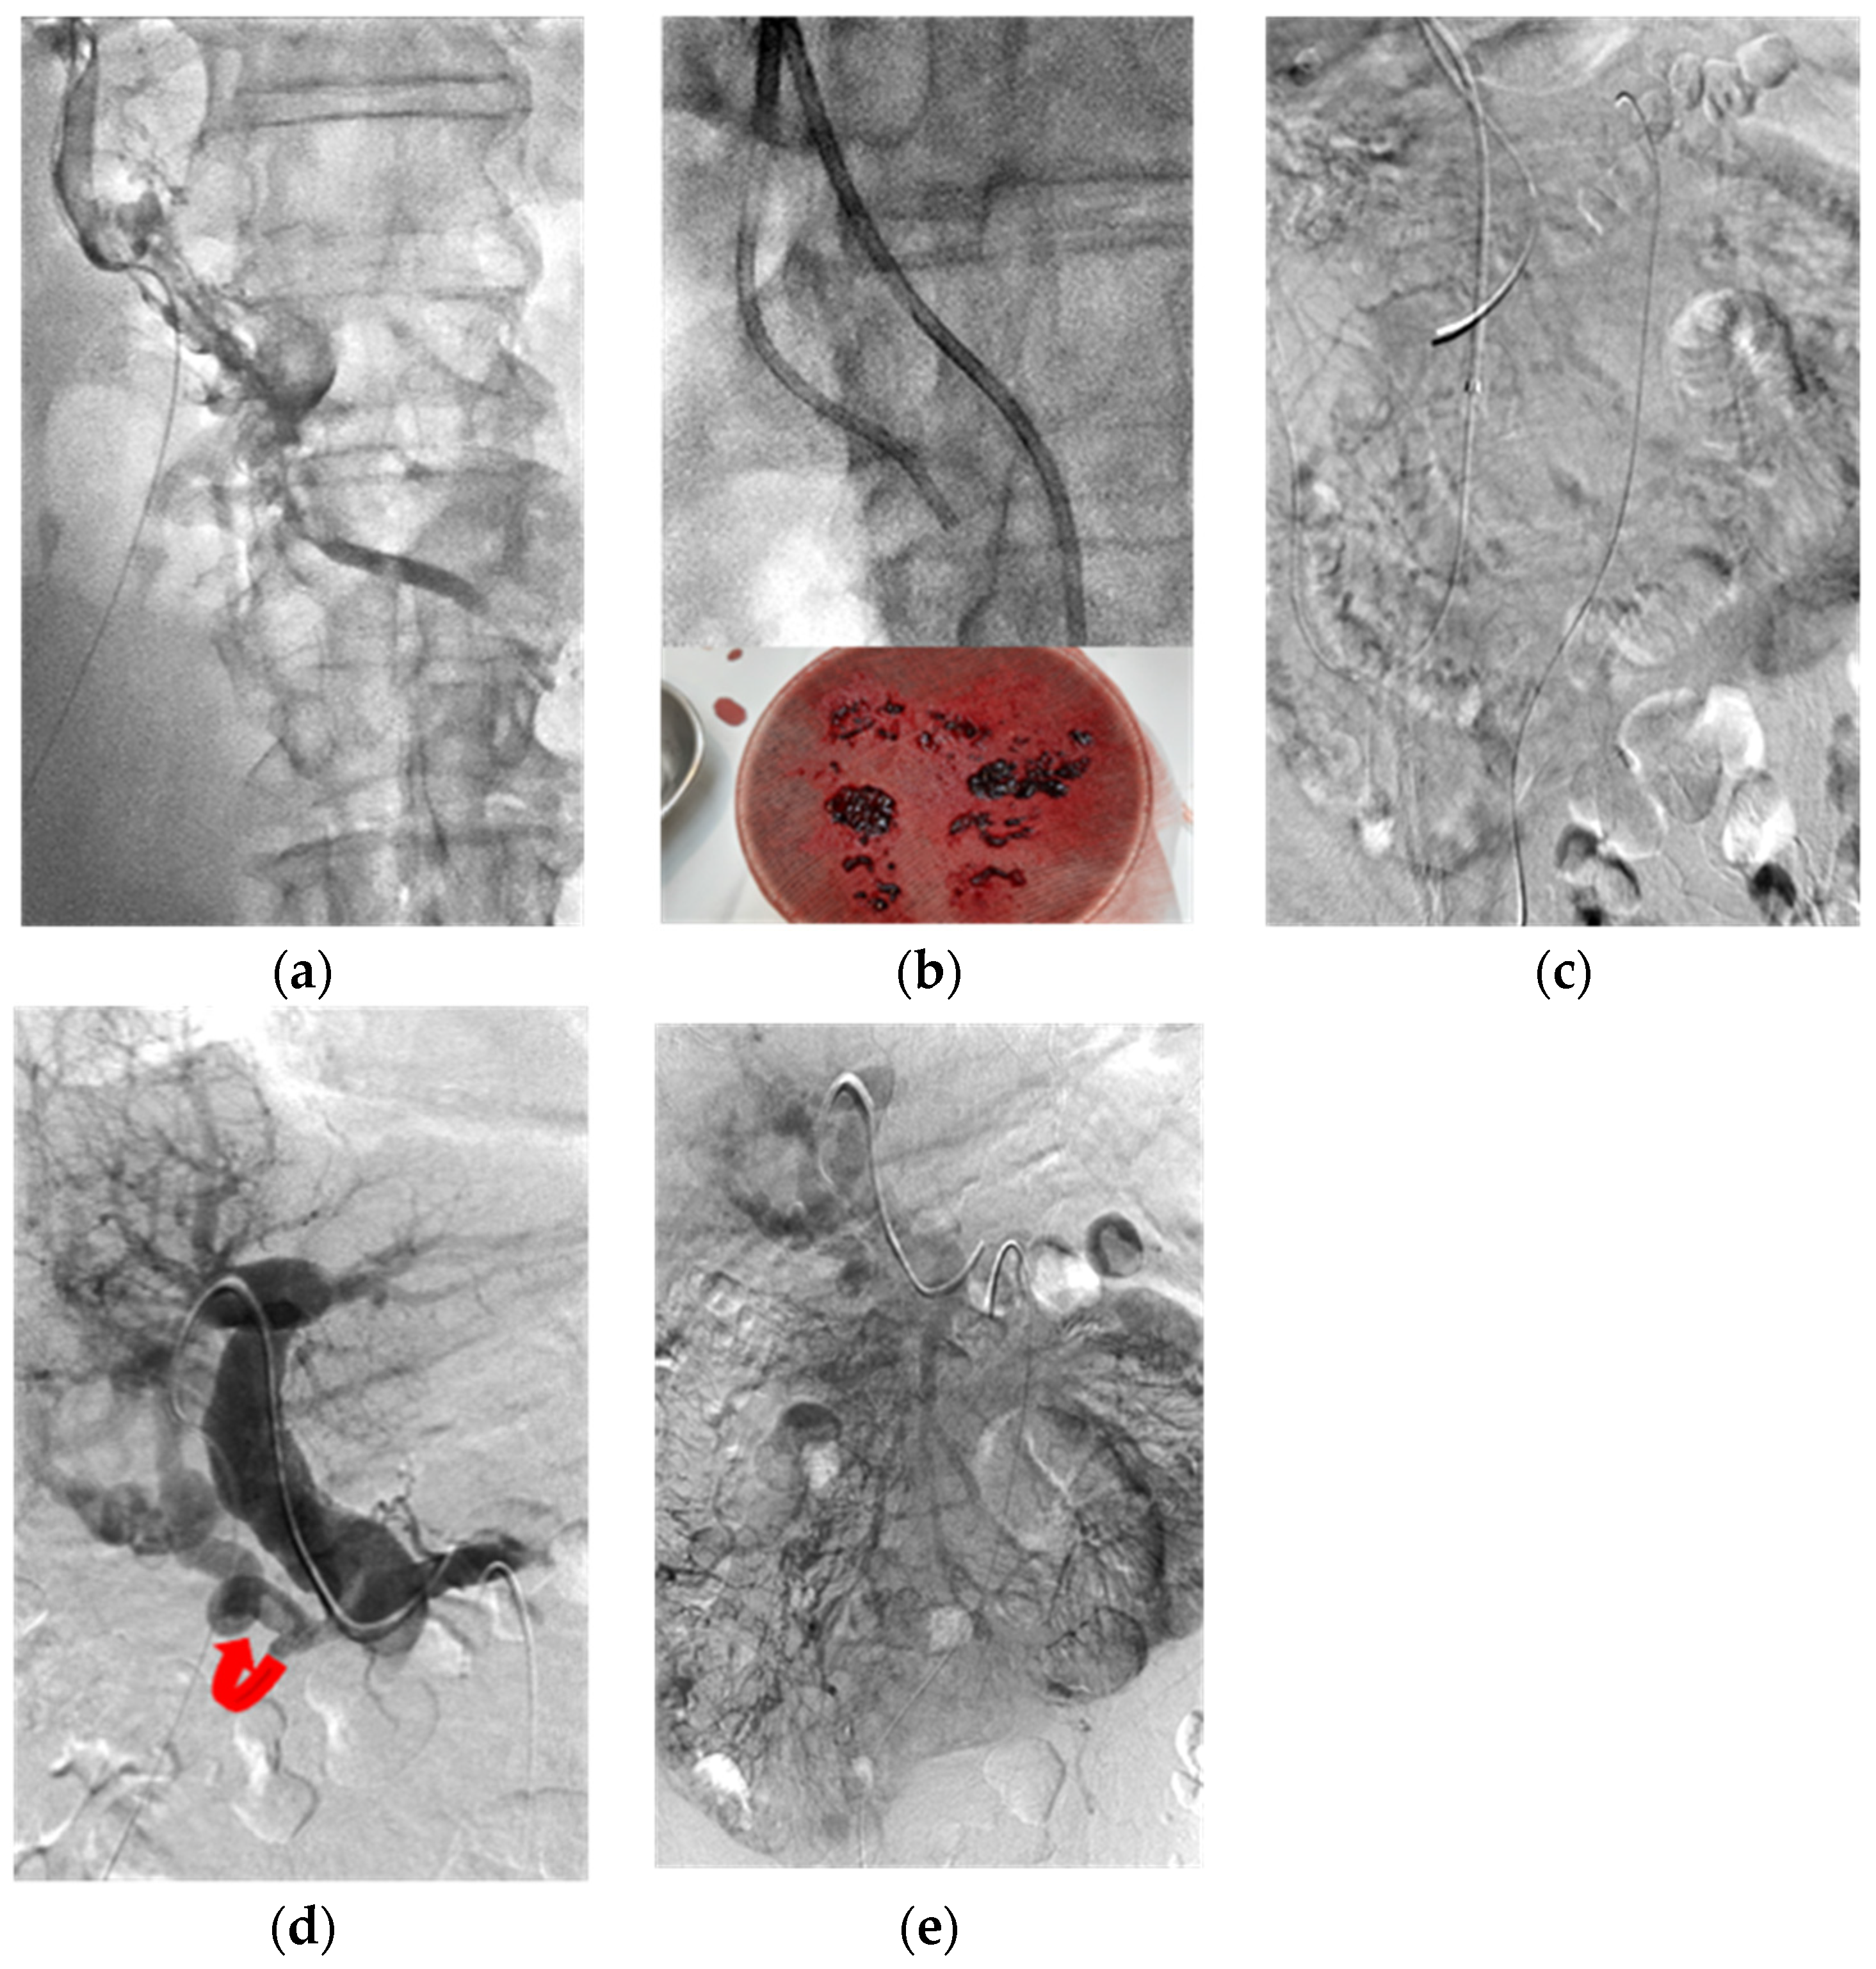

2. Patients and Methods

3. Thrombolysis Technique